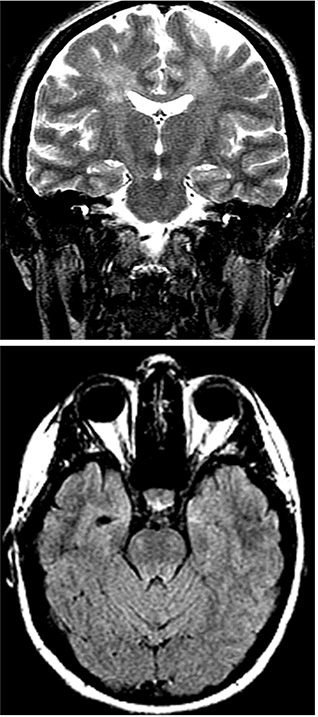

Pathologic studies in a limited number of cases have disclosed a relatively stereotyped pattern of reduced numbers of Betz cells in the frontal and prefrontal motor cortex, degeneration of the corticospinal tracts, also evident on MRI (Figure 3), and preservation of motor neurons in the spinal cord and brainstem (20).

Fig 3

Figure 3. T2-weighted coronal (3a, top) and FLAIR axial (3b, bottom) MRI showing signal changes that reflect Wallerian degeneration in the corticospinal tracts (Courtesy Dr. Rita G. Bhatia).

In patients with prominent corticospinal signs, the MRI may show slight atrophy of the motor cortex and signal changes indicating Wallerian degeneration of the corticospinal tracts (Figure 3). These changes may be diagnostically useful when the presence of severe LMN deficit makes pyramidal tract signs unobvious. Corticospinal tract degeneration appears as an increased FLAIR and T2 signal intensity in the posterior limb of the internal capsule, descending motor tracts of the brainstem, and spinal cord (13). These MRI signs however are generally subtle and often missed.